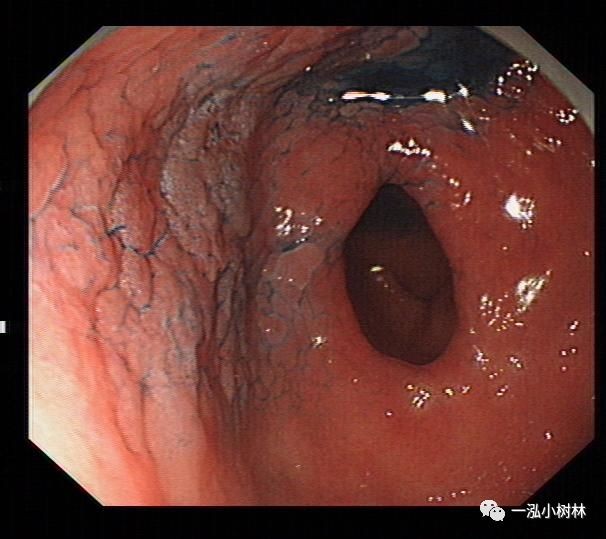

萎缩性胃炎普通内镜表现:黏膜苍白,黏膜下血管透见,黏膜皱襞细小或消失,病变黏膜粗糙呈颗粒状或结节状,伴有肠化时轻者常不可见,重者可见斑片状、点状米粒大小白色或灰白色隆起改变,另外萎缩黏膜与正常黏膜可见到萎缩边界。

例2

女性,60岁,慢性萎缩性胃炎伴肠上皮化生,Hp+